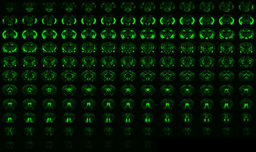

The description of metformin's anxiolytic mechanism

Schematic illustration of the AMPK-dependent anxiolytic effect of metformin by mPFC GABAergic microcircuit action.